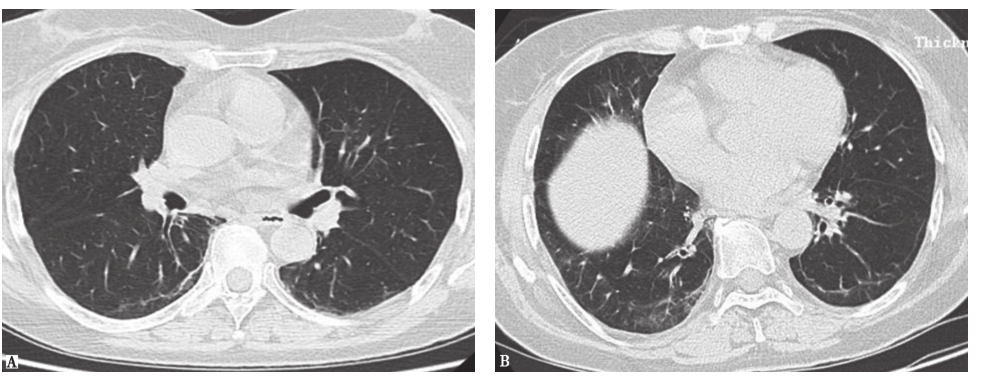

图5放射性肺炎胸部影像学表现

男性患者,59岁,右下肺鳞癌放疗结束后6周(48Gy)出现双肺弥漫渗出。HRCT见右下叶癌性空洞,空洞周围实变(A),双肺磨玻璃样渗出(B)